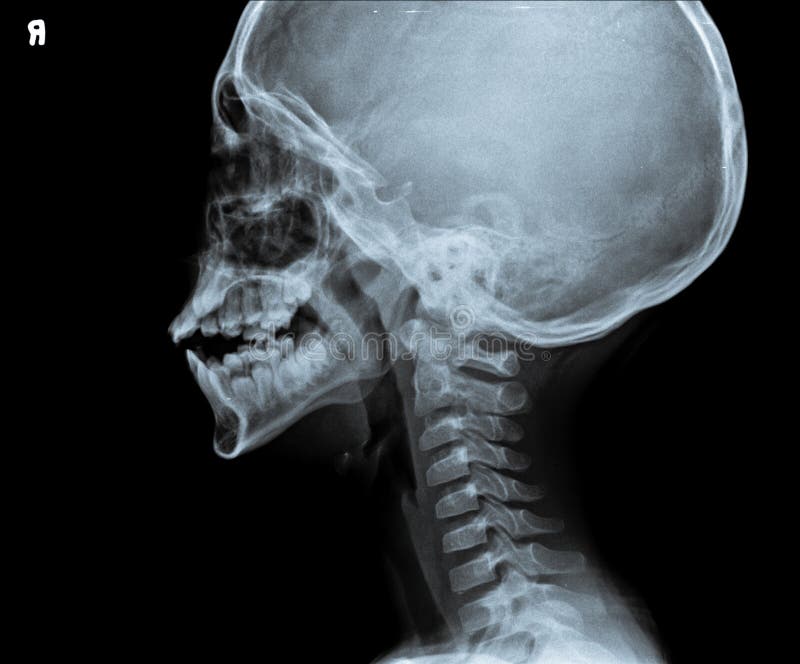

Radiografia Della Testa E Del Collo Foto Foto Stock Gratis E Royalty Free Da Dreamstime

Radiografia Della Testa E Del Collo Fotografia Stock Immagine Di Malattia Osso